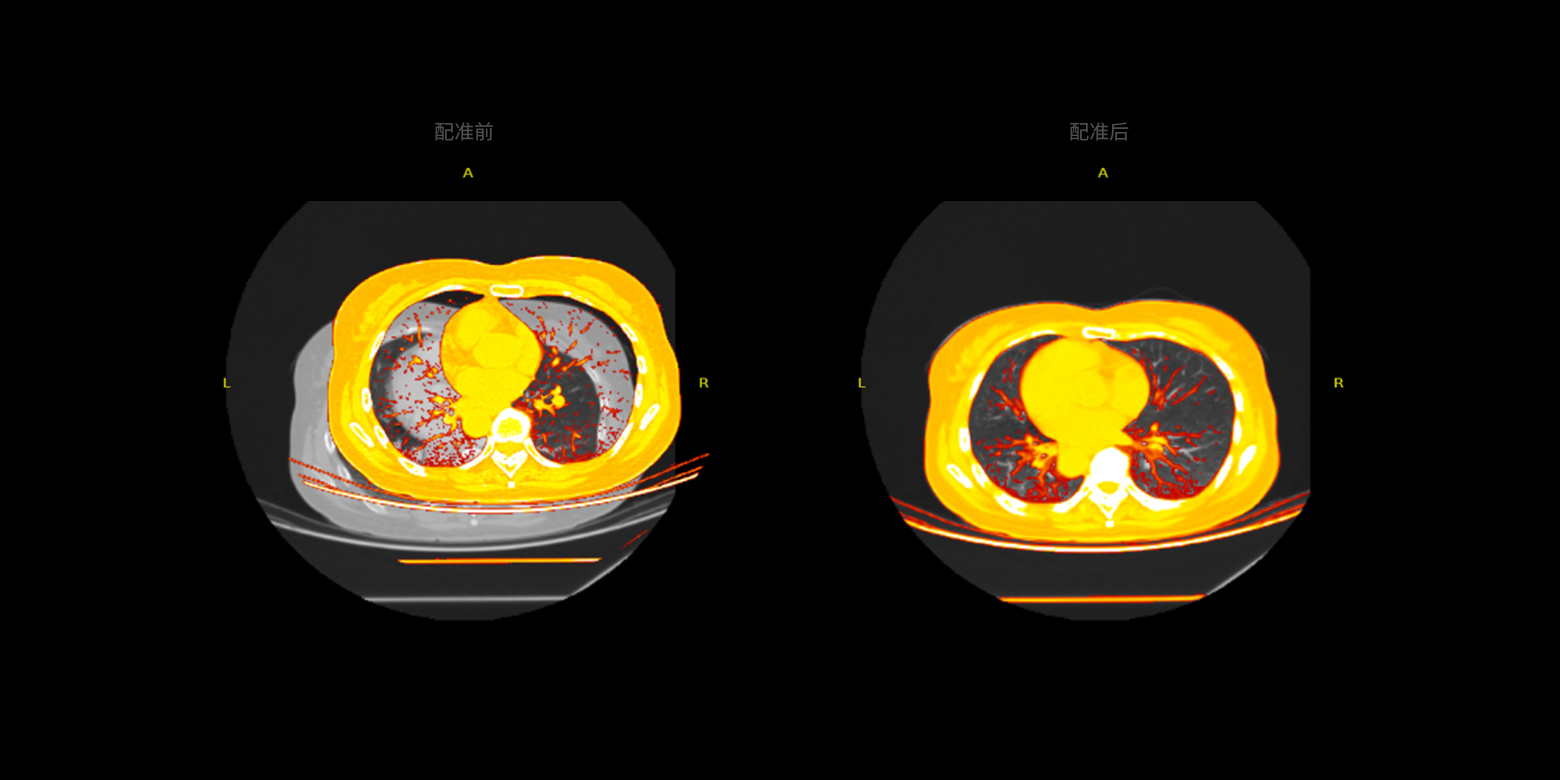

多模态数据的配准

支持同一部位或器官的 CT、MRI、PET 等多模态数据的配准,实现不同模态或不同序列数据之间精确的图像融合,从而能够更精准地对病灶进行定性分级或定量分析。

多模态数据的配准

支持同一部位或器官的 CT、MRI、PET 等多模态数据的配准,实现不同模态或不同序列数据之间精确的图像融合,从而能够更精准地对病灶进行定性分级或定量分析。